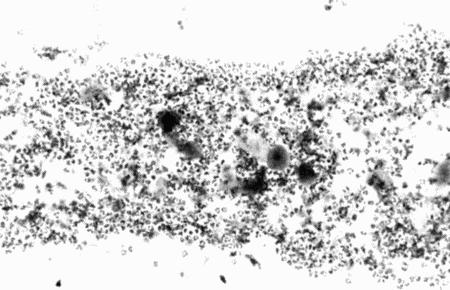

При вагините у взрослых животных проводят исследование содержимого влагалища, тогда как у молодых сук с недоразвитым влагалищем материал для бактериологического и цитологического исследования берут с половых губ. Нет смысла причинять им дополнительные неудобства, тем более что это не дает никаких преимуществ в постановке диагноза. Окрашивание мазков по Giemsa или Diff-Quik выявляет повышенное содержание полиморфноядерных лейкоцитов (фиг. 4.7). Данные бактериологического, гематологического и биохимического анализов обычно не информативны. При проведении вагиноскопии у молодых сук может возникнуть необходимость в применении седативных препаратов, к тому же исследование позволяет обнаружить лишь покраснение и наличие выделений; указанные обстоятельства ограничивают применение метода.

Фиг. 4.7.

Вагинальная цитология 7-месячной суки с ювенильным вагинитом. Следует отметить большое количество полиморфноядерныхлейкоцитов (см. Приложение)